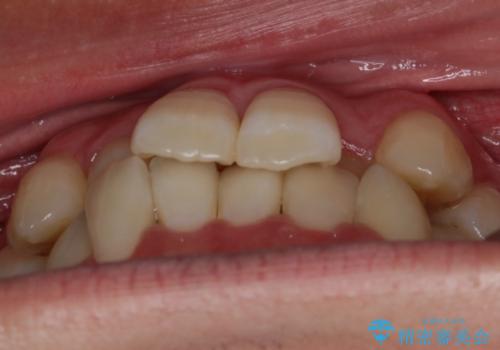

【非抜歯】八重歯を治す マウスピース矯正

- 前歯のガタつきの治療を主訴にご来院されました。

目立たない装置をとのご要望があったため、検査結果をふまえてインビザラインでの非抜歯矯正を行うこととなりました。

非抜歯での治療

抜歯をせずに歯のガタつきを治すためのスペースを作るために

①歯の遠心移動

②歯列弓の拡大

③IPR(歯を少し小さく削る)

この3つの方法を複合的に組み合わせて治療を行いました。

抜歯をせずとも笑った時の歯の見え方が劇的に変化していることが分かります。